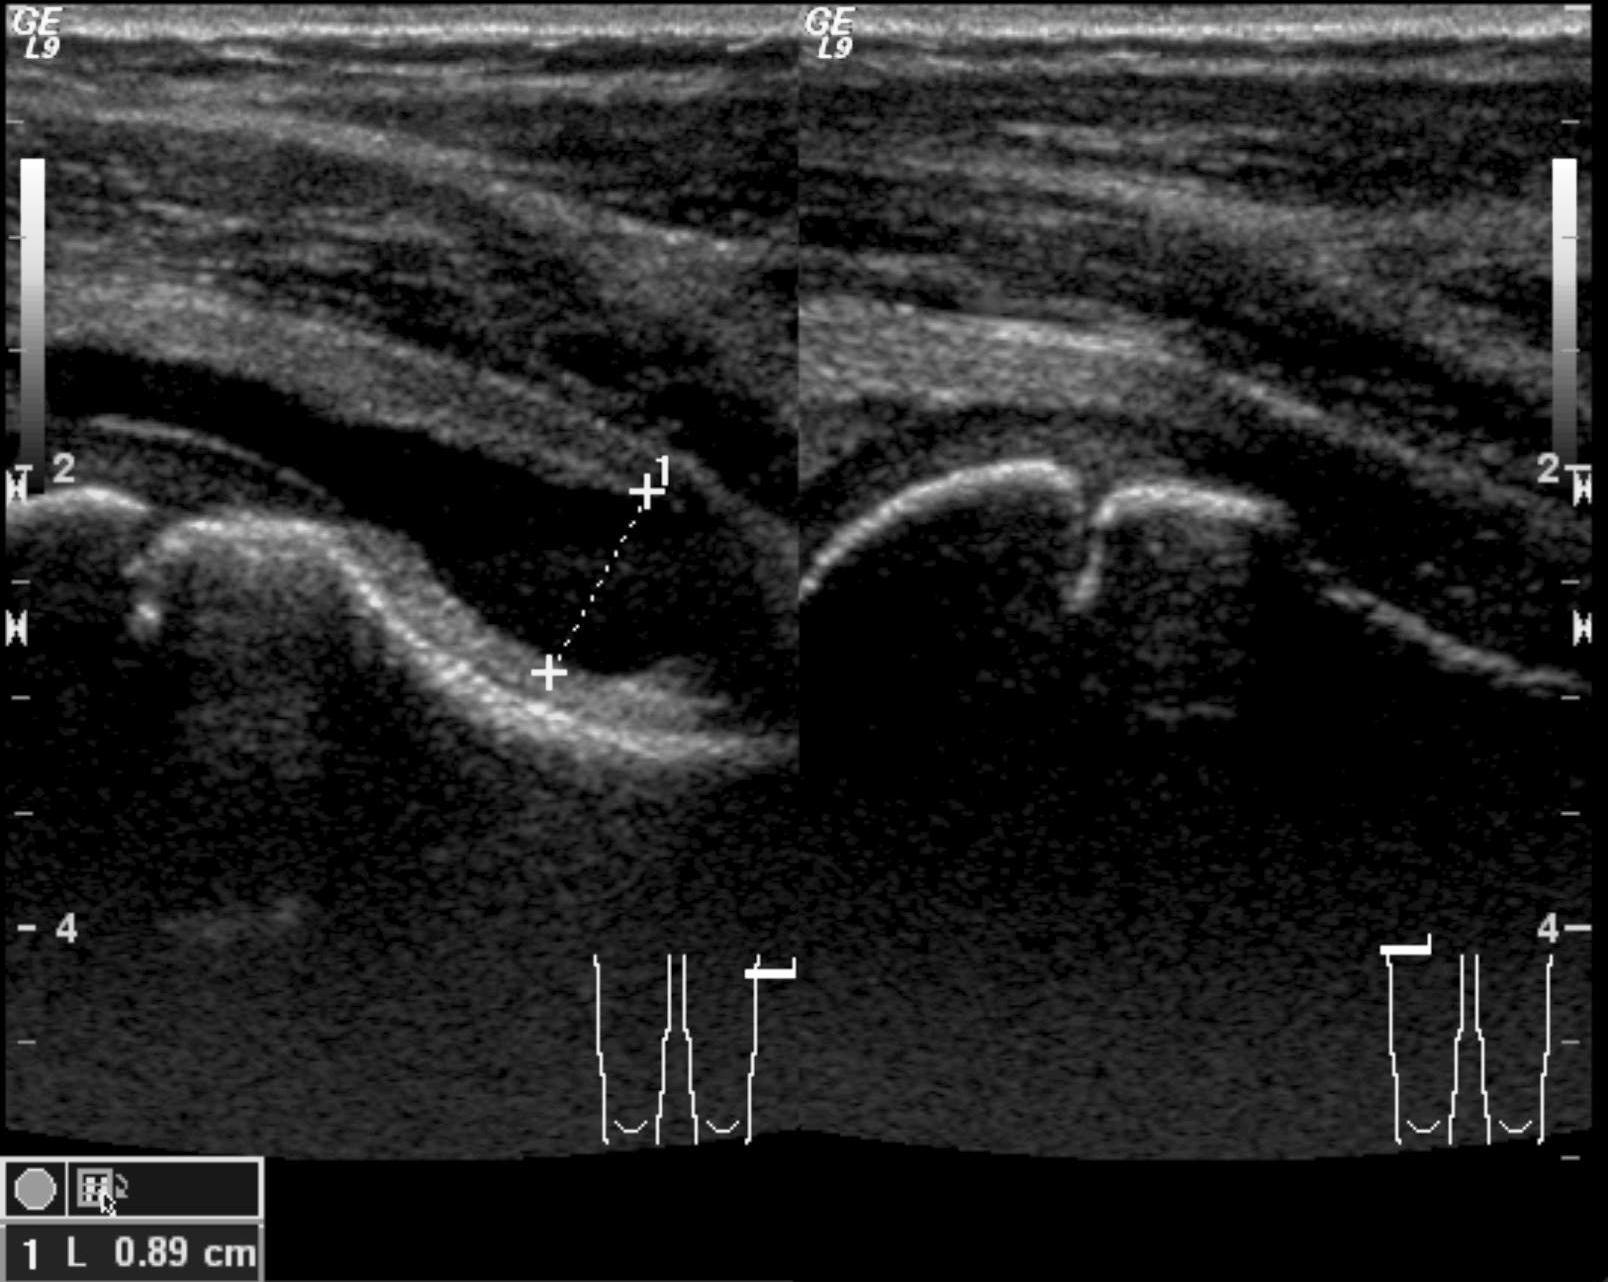

12a: Abdominal US: the pyloric canal is extended, its wall is thickened. Pylorus stenosis, longitudinal view.

Image

12.b. Axial cross section.

Hypertrophic pyloric stenosis (HPS). As a result of the hypertrophy and hyperplasia of the pyloric musculature a secondary stenosis can occur, that usually leads to symptomatic states in 3-6 weeks old infants. It primarily occurs in boys as frequent, progressive, nonbilious, projectile vomiting. On ultrasonography an enlarged (15mm or more), thick walled (3mm or more) pylorus can be seen in both longitudinal and in axial cross section.